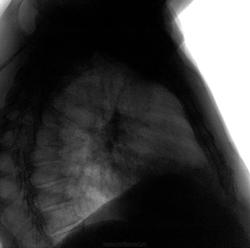

И плевральные, и сердечные.

Справа думаю осумкованный, заднепристеночный пневмоторакс.

нет дела тут легочные а именно это дисковидные ателектазы,что имеет право иметь место ,особенно после перенесенных операций __))))

Нет -дела здесь плевральные.И вовсе не дисковидные, и не ателектазы.

без существенной динамики. Во время оперативного вмешательства был пневмоторакс, потом дренирование, выполт в плевральную полость.